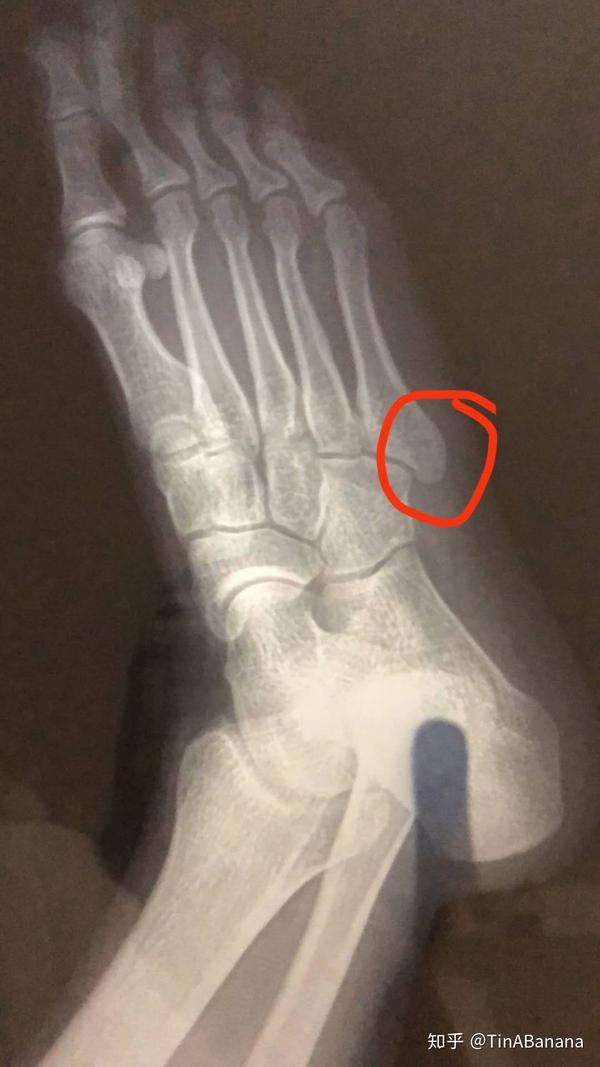

骨折记 — 第五跖骨基底骨折 - 知乎

宁折不弯——左脚第五跖骨基底粉碎性骨折 随记三个月 - 知乎

第五跖骨基底部骨折42天